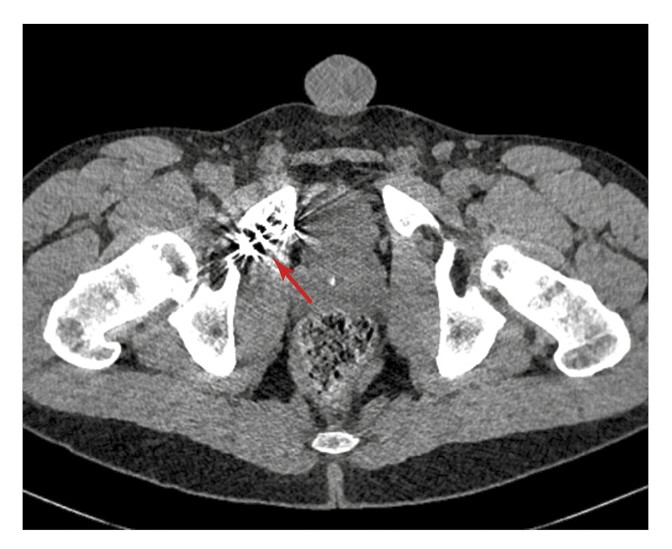

С целью подтверждения венозной утечки и оценки венозной анатомии половой системы пациенту проведена МСКТ-кавернозография. Фармакологическую стимуляцию осуществляли посредством введения 10 мкг простагландина интракавернозно. Получены изображения в нативную фазу (до введения контрастного вещества), а также через 30 с, 1, 3 и 5 мин после интракавернозного введения контрастного препарата (йогексола 350 мг/мл, 50 мл). По данным КТ в области наружной и внутренней поверхностей правой лобковой кости определяются множественные гиперденсивные структуры, вероятно, эмболизационные спирали (рис. 2).

Рис. 2. Данные МСТК-кавернозографии больного К. Стрелкой указаны гиперденсивные инородные структуры (вероятно, спирали) в области правой лобковой кости.